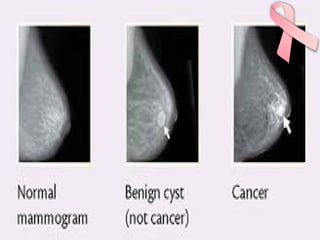

MAMMOGRAPHY

Mammography Technique